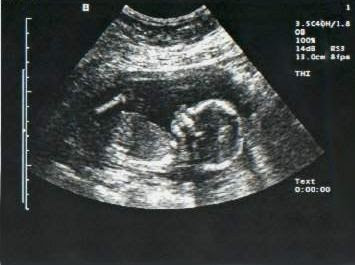

Bueno pues ahí está la noticia, estoy embarazada de tres meses, vais a ser abuelos, espero de corazón, que os entusiasme la idea, tanto como a su padre y a mi. Y ya podéis ver su ecografía de las 12 semanas.